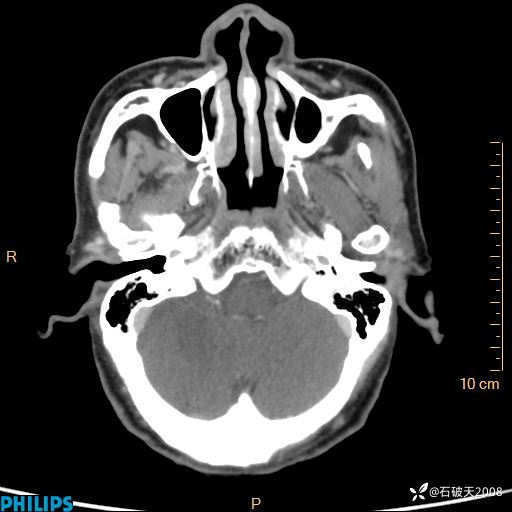

平扫